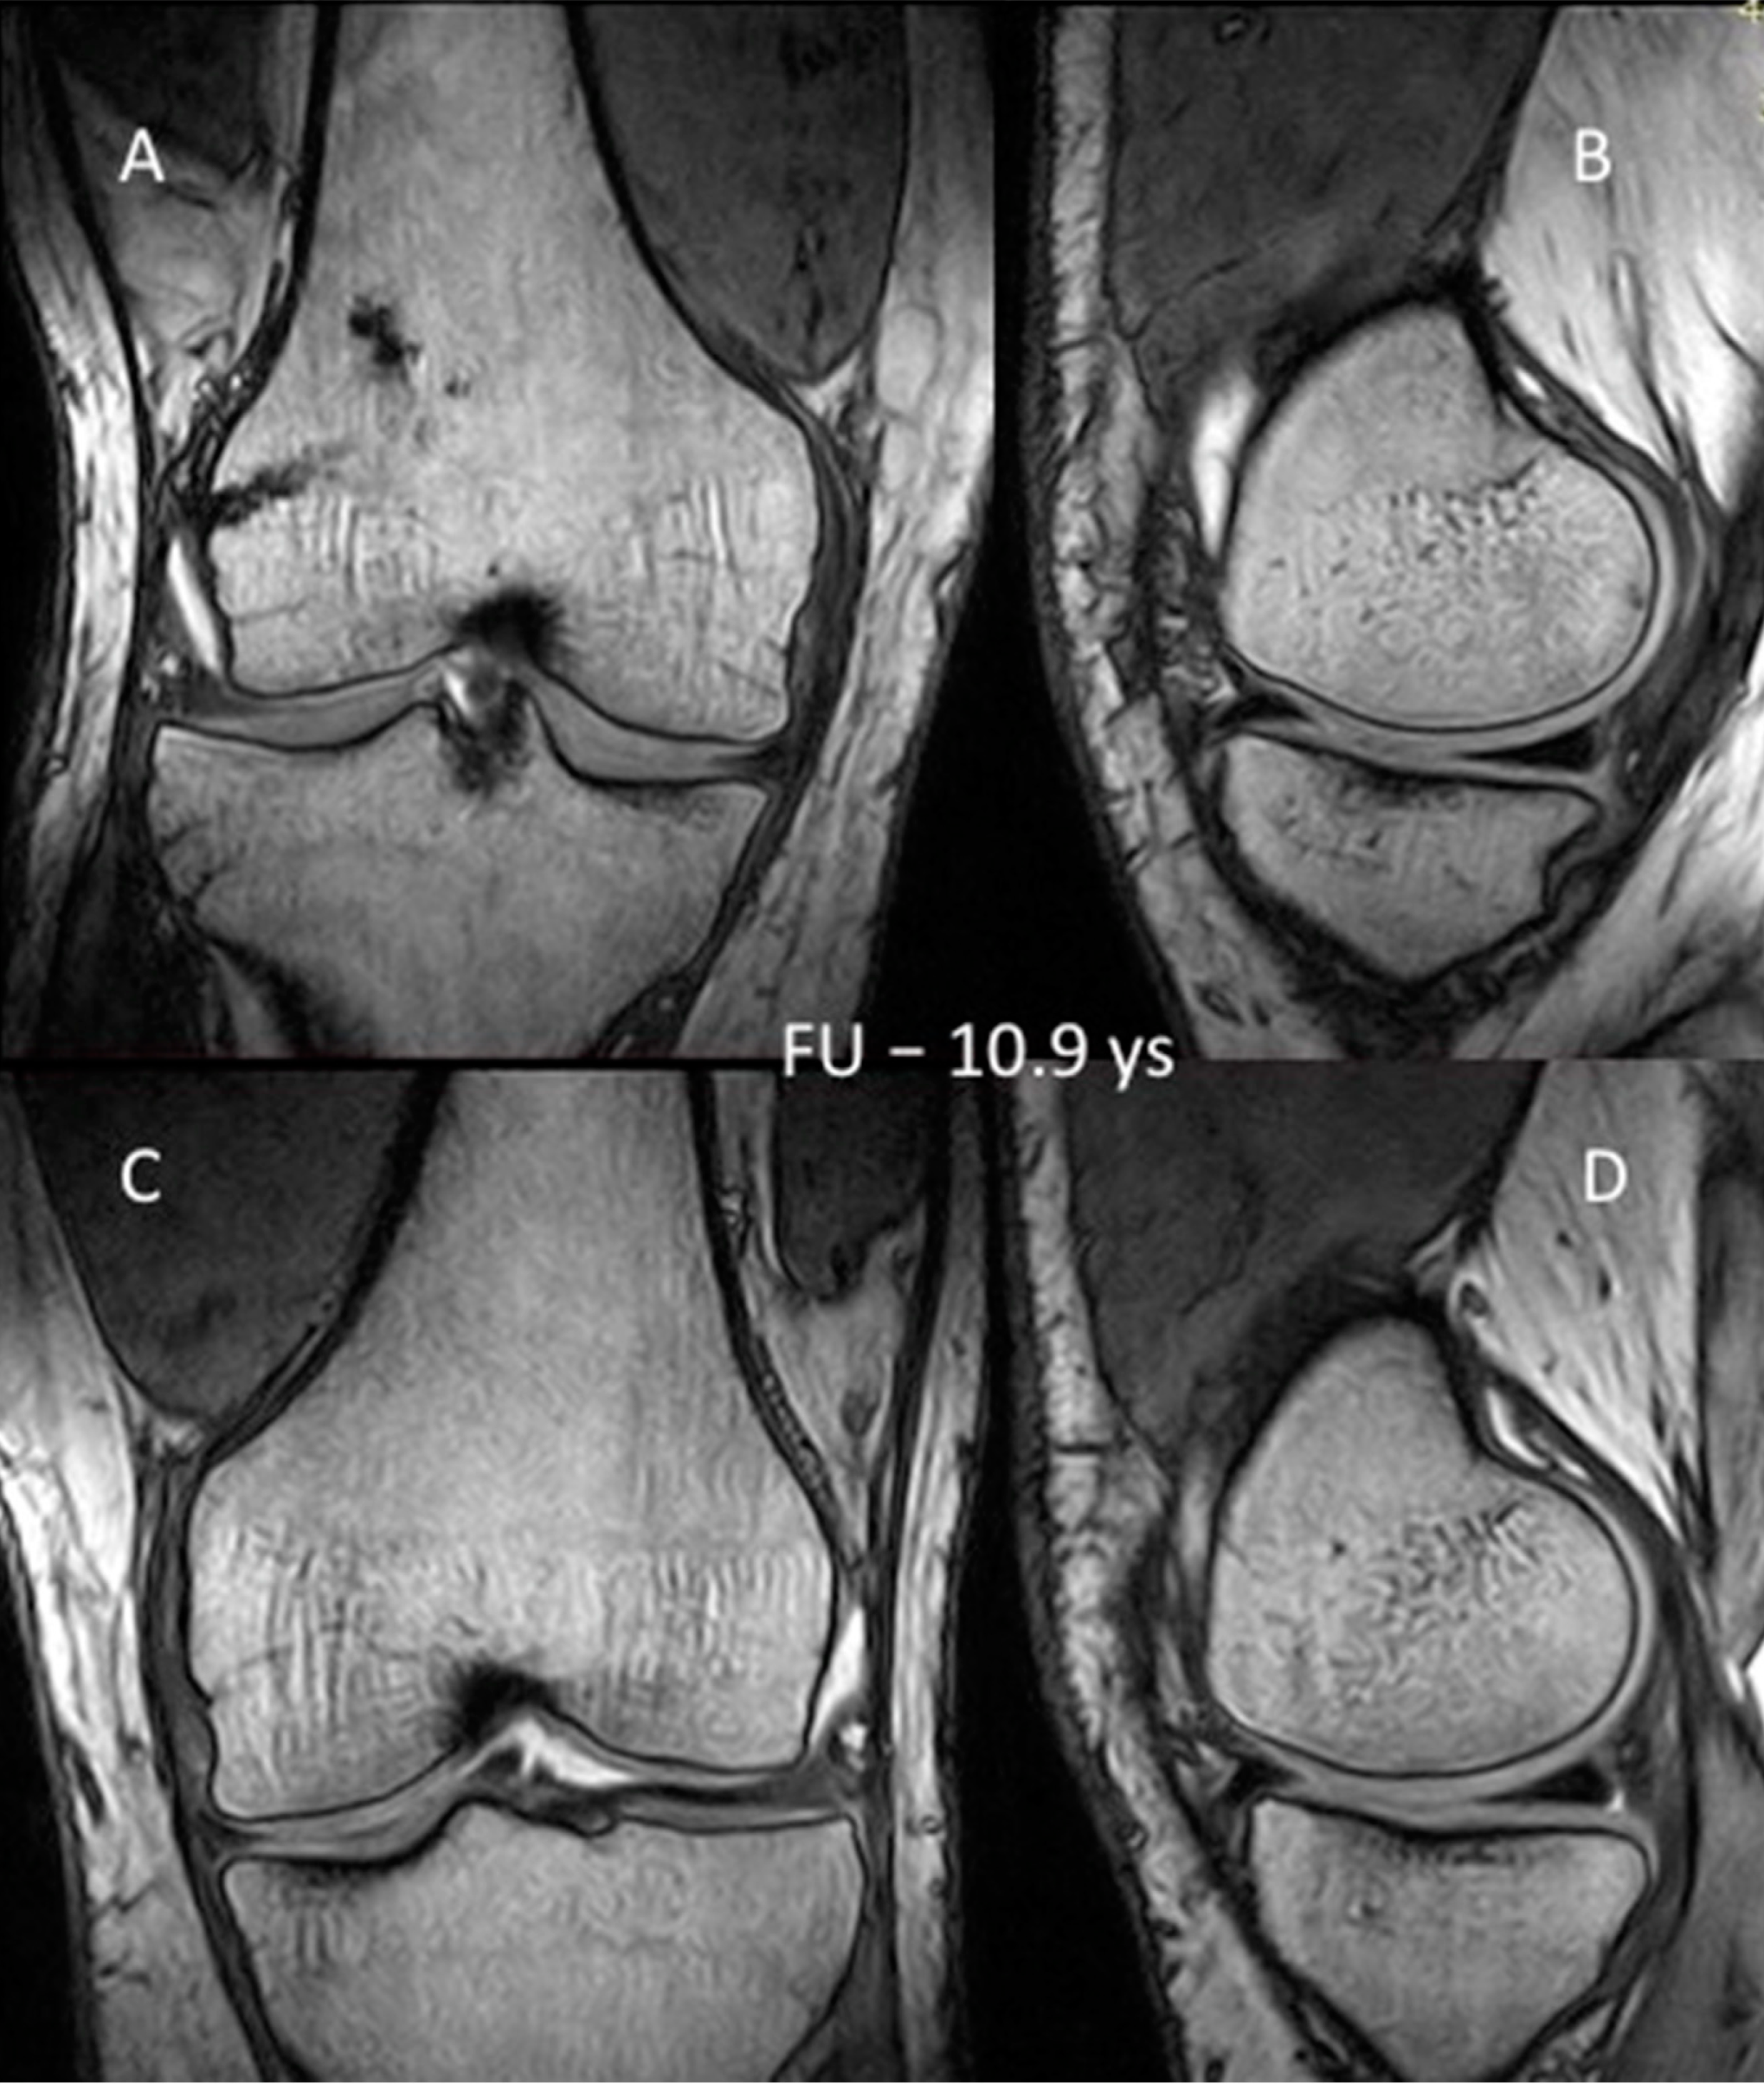

3.3. MRI Evaluation of the Cartilage

| First follow-up period (years) | 11.7 | 12.3 | 9.8 | 10.4 | 10.2 | 10.9 ± 0.94 |

| Second follow-up period (years) | 18.6 | 19.1 | 16.6 | 17.3 | 17.4 | 18.1 ± 0.94 |